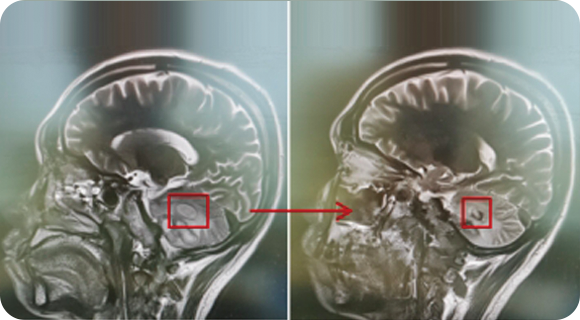

精通颅内动脉瘤介入栓塞和手术夹闭双技术,系统掌握脑动静脉畸形、颈内动脉海绵窦漏、硬脑膜动静脉漏等颅内血管疾病的诊疗和手术,精通颈动脉、椎动脉狭窄的血管内重建技术,以及颈动脉狭窄的内膜剥脱手术技术。在颅内肿瘤、椎管内肿瘤、颅脑损伤、高血压脑出血等疾病的诊治和手术,脑功能性疾病立体定向手术治疗等方面也积累了丰富的经验。